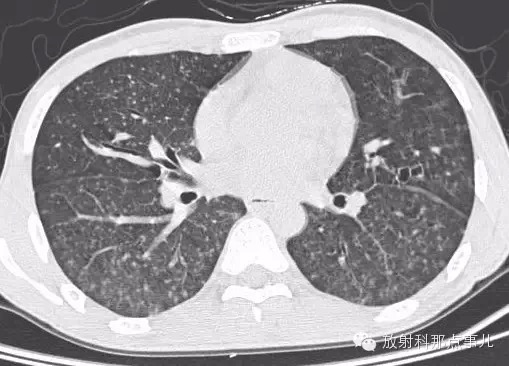

影像表现

1.胸片示双肺网状纹理,弥漫分布粟粒样病灶,由上至下病灶逐渐增多。

2.CT示双肺网状纹理,弥漫分布粟粒样病灶;HRCT示左肺上叶舌段肺气囊。